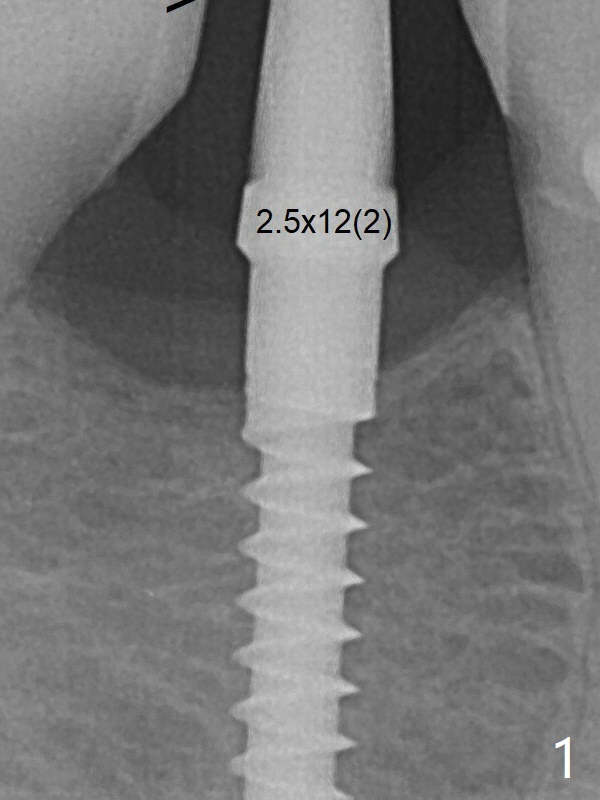

The mesial surface of the tooth #31 is reduced prior to osteotomy (Fig.1 >) so that the mesiodistal width of the edentulous area is 4.5 mm. An incision is made instead of tissue punch because of the narrow keratinized gingiva. The potential osteotomy site happens to have nonkeratinized tissue. Because of apparently sufficient clearance from the Inferior Alveolar Canal (Fig.2 red dashed line), the implant is placed ~ 1 mm deeper later. After suturing, periodontal dressing is applied. At patient's request, a provisional is fabricated with occlusal clearance 26 days postop. The occlusal surface of the provisional perforates 3.5 months postop with the provisional having pressed the gingiva, which is consistent with crestal bone loss (Fig.3). There is minimal bone loss 11 months post cementation; in fact the bone density around the coronal portion of the implant increases (Fig.5). Trajectory PA Last Next Xin Wei, DDS, PhD, MS 1st edition 06/01/2018, last revision 09/18/2019